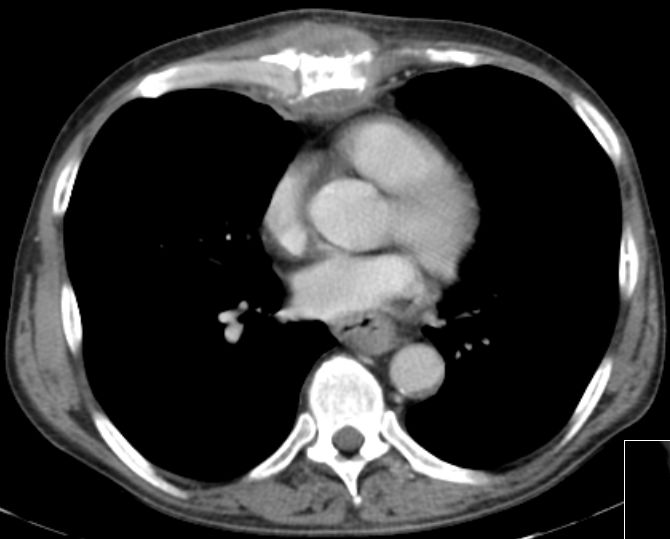

54jähriger Kellner mit einem Oesophagus – Karzinom cT2, welches 2 cm unterhalb der Karina beginnt. Längenausdehnung 6 cm.

Histologie: invasives gering verhornendes Plattenepithelkarzinom, G2.

Klinisch zunehmende Dysphagie.

Das CT zeigt vergrößerte Lymphknoten am Truncus coeliacus (nicht histologisch verifiziert)![]() | ||